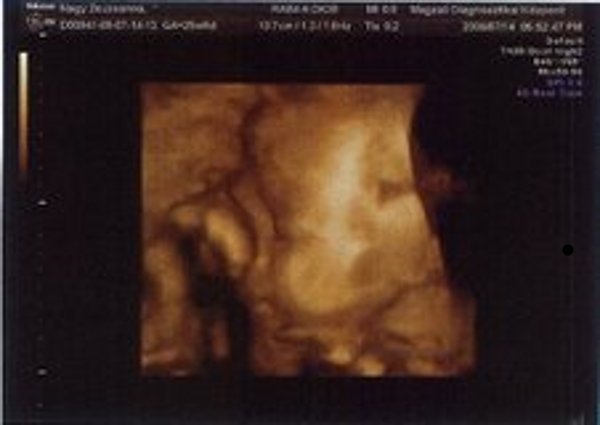

Kistörpe! Tényleg nagyon rohan az idő. Gratula Nektek! Majd hozz képet az uh-ról!